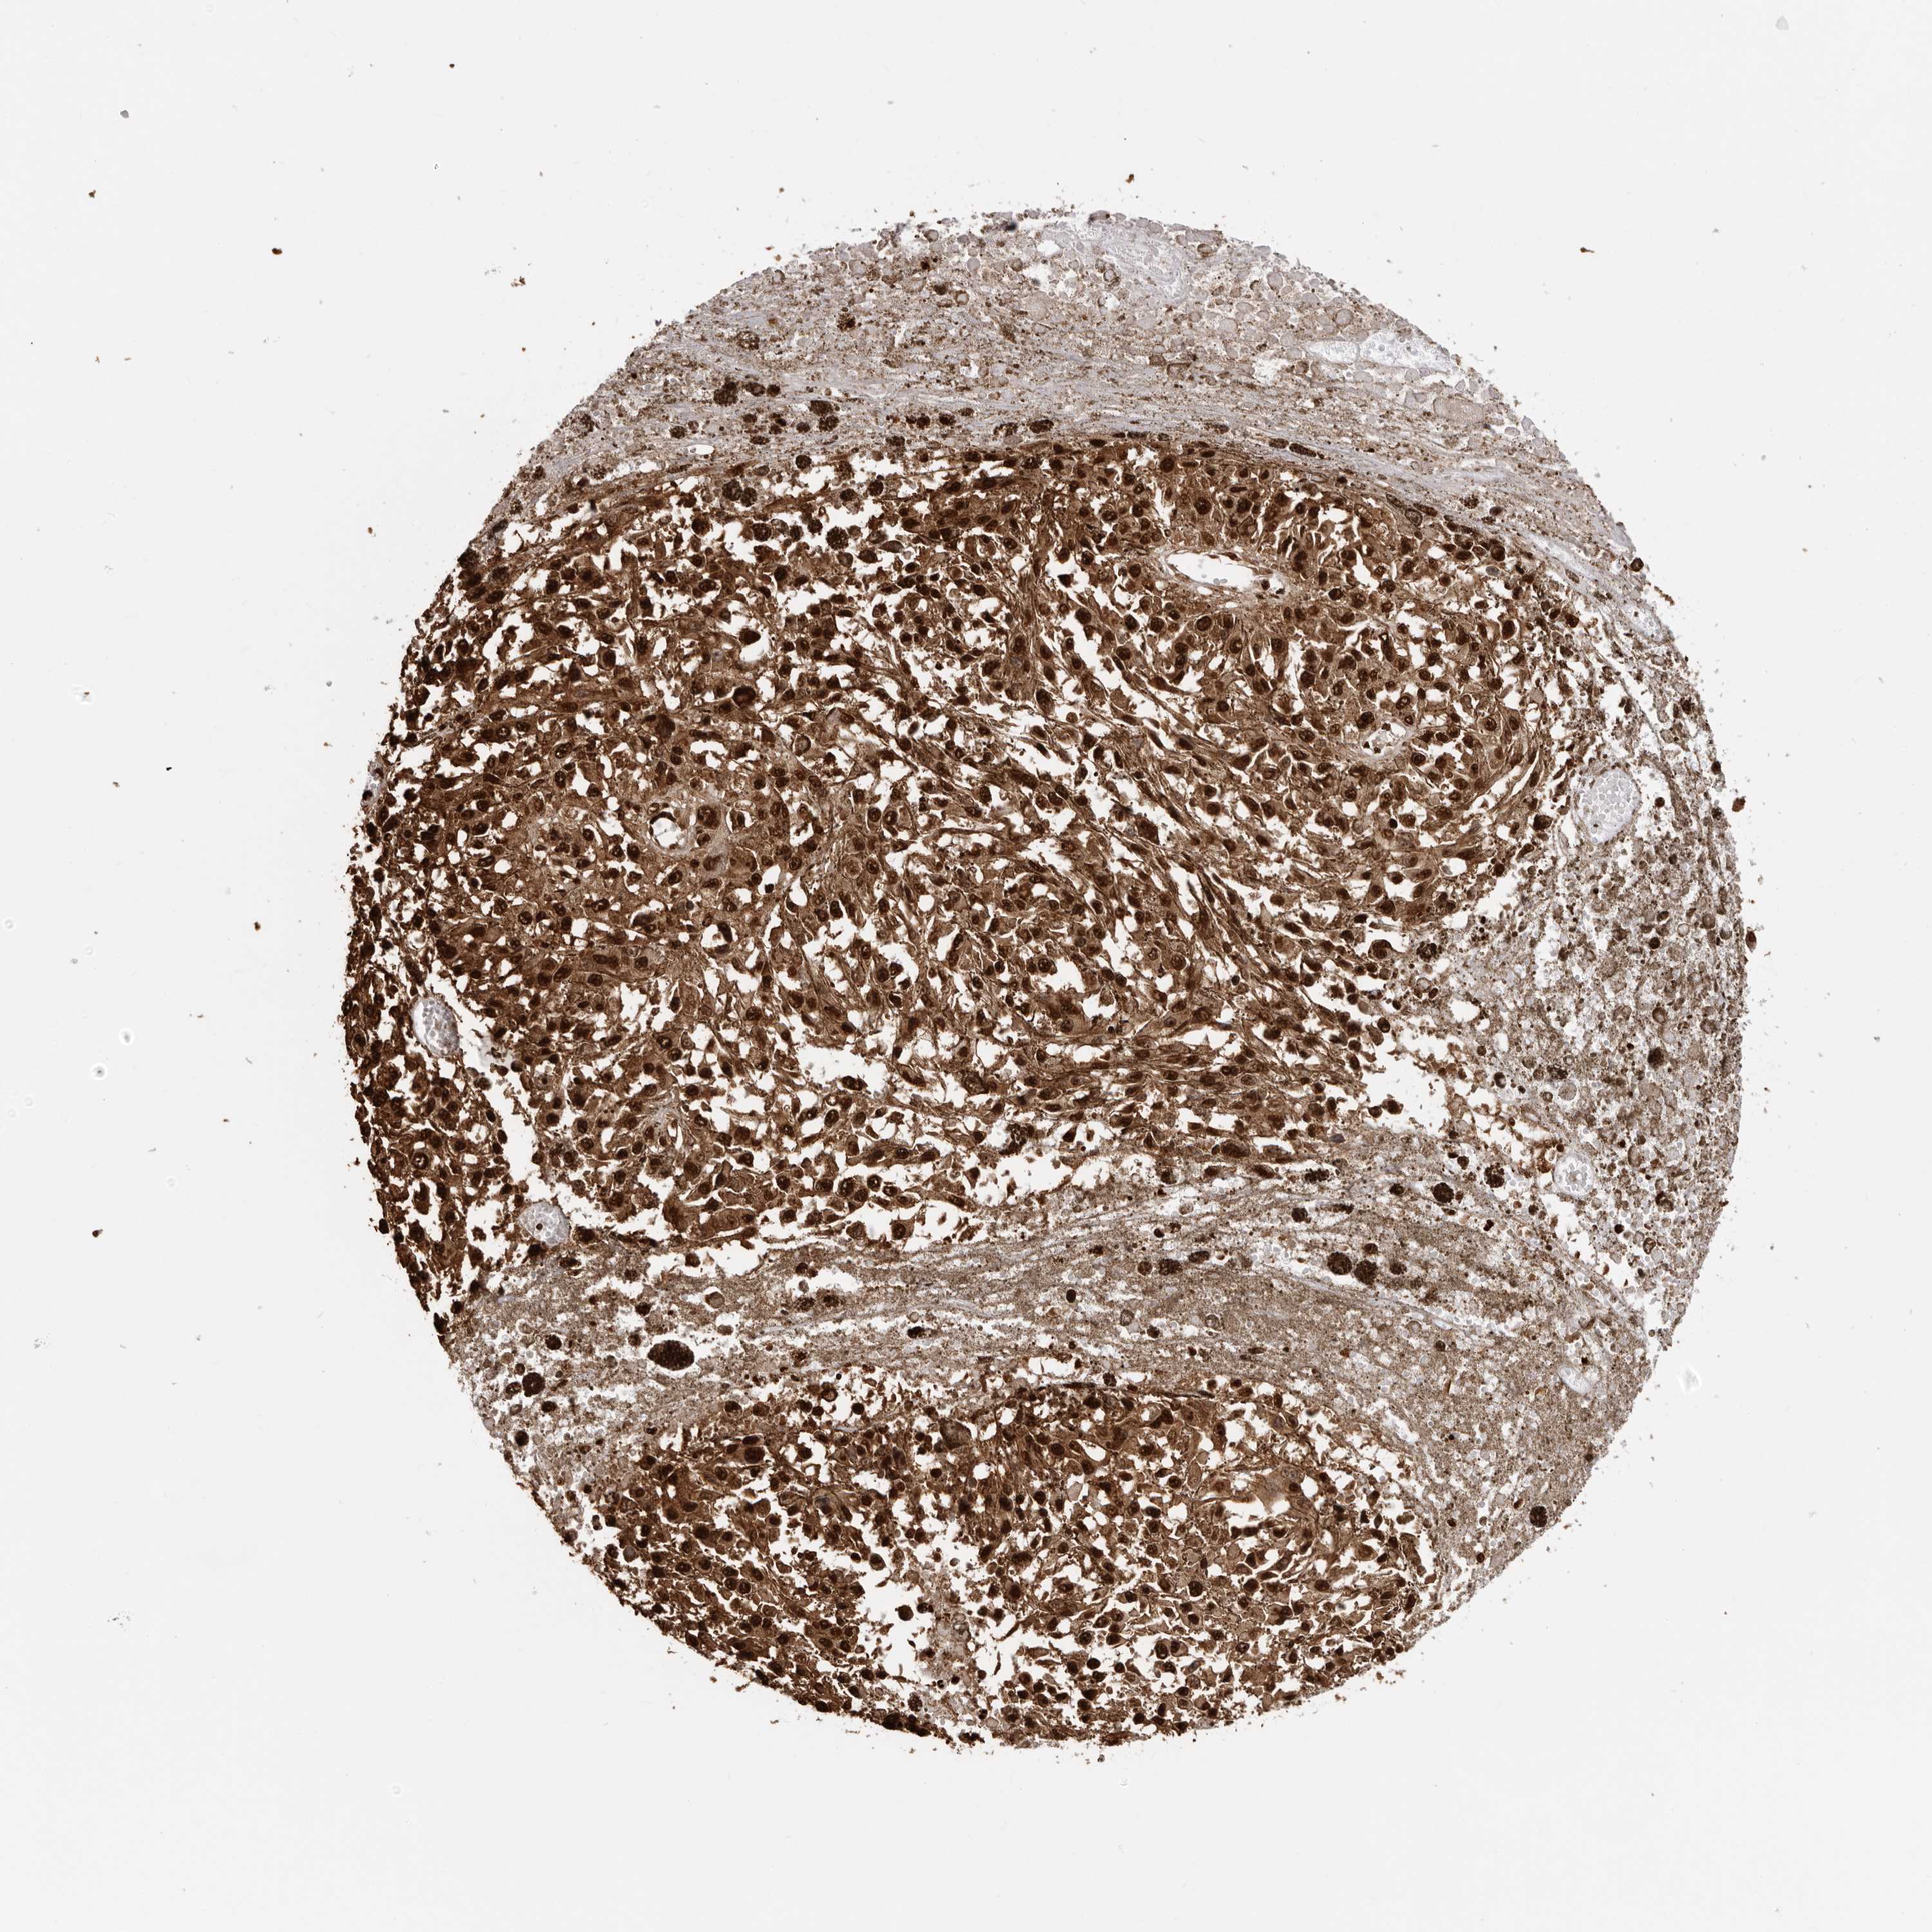

MELANOMA - Protein expressioni

A mouse-over function shows sample information and annotation data. Click on an image to view it in a full screen mode. Samples can be filtered based on level of antibody staining by selecting one or several of the following categories: high, medium, low and not detected. The assay and annotation is described here.

Note that samples used for immunohistochemistry by the Human Protein Atlas do not correspond to samples in the TCGA dataset.

Antibody stainingi

Antibody staining in the annotated cell types in the current human tissue is reported as not detected, low, medium, or high, based on conventional immunohistochemistry profiling in selected tissues. This score is based on the combination of the staining intensity and fraction of stained cells.

Each image is clickable and will lead to virtual microscopy that enables deeper exploration of all samples and also displays staining intensity scores, fraction scores and subcellular localization as well as patient and tissue information for each sample.

Antibody HPA024037

Antibody HPA065325

Antibody HPA074591

Antibody CAB025417

Staining

High

Medium

Low

Not detected

Intensity

Strong

Moderate

Weak

Negative

Quantity

>75%

75%-25%

<25%

None

Location

Nuclear

Cytoplasmic/membranous

Cytoplasmic/membranous,nuclear

Malignant melanoma, NOS

Malignant melanoma, Metastatic site